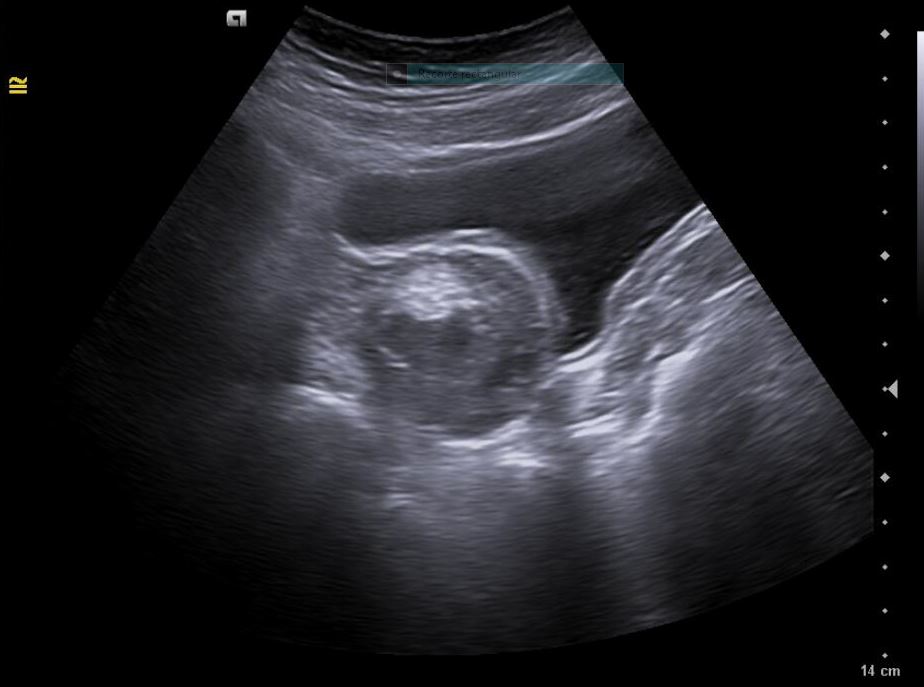

Descripción de los hallazgos ecográficos y las imágenes más relevantes para la resolución del caso

Diagnóstico inicial: Teratoma ovárico derecho versus cuerpo lúteo hemorrágico.

Diagnóstico diferencial: endometriosis, quiste funcional, quiste dermoide.

La paciente es valorada en consulta presencial de ginecología. Ecografía vaginal confirma: